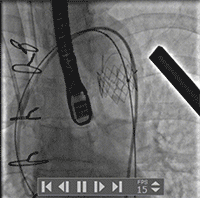

主瓣造影

左室造影

手术超声结果

主瓣

术后

术前术后流速压差对比,术前最大速度464cm/s,平均速度316cm/s,最大压力梯度86mmHg,平均压力梯度46mmHg;术后最大速度254cm/s,平均速度151cm/s,最大压力梯度26mmHg,平均压力梯度11mmHg: